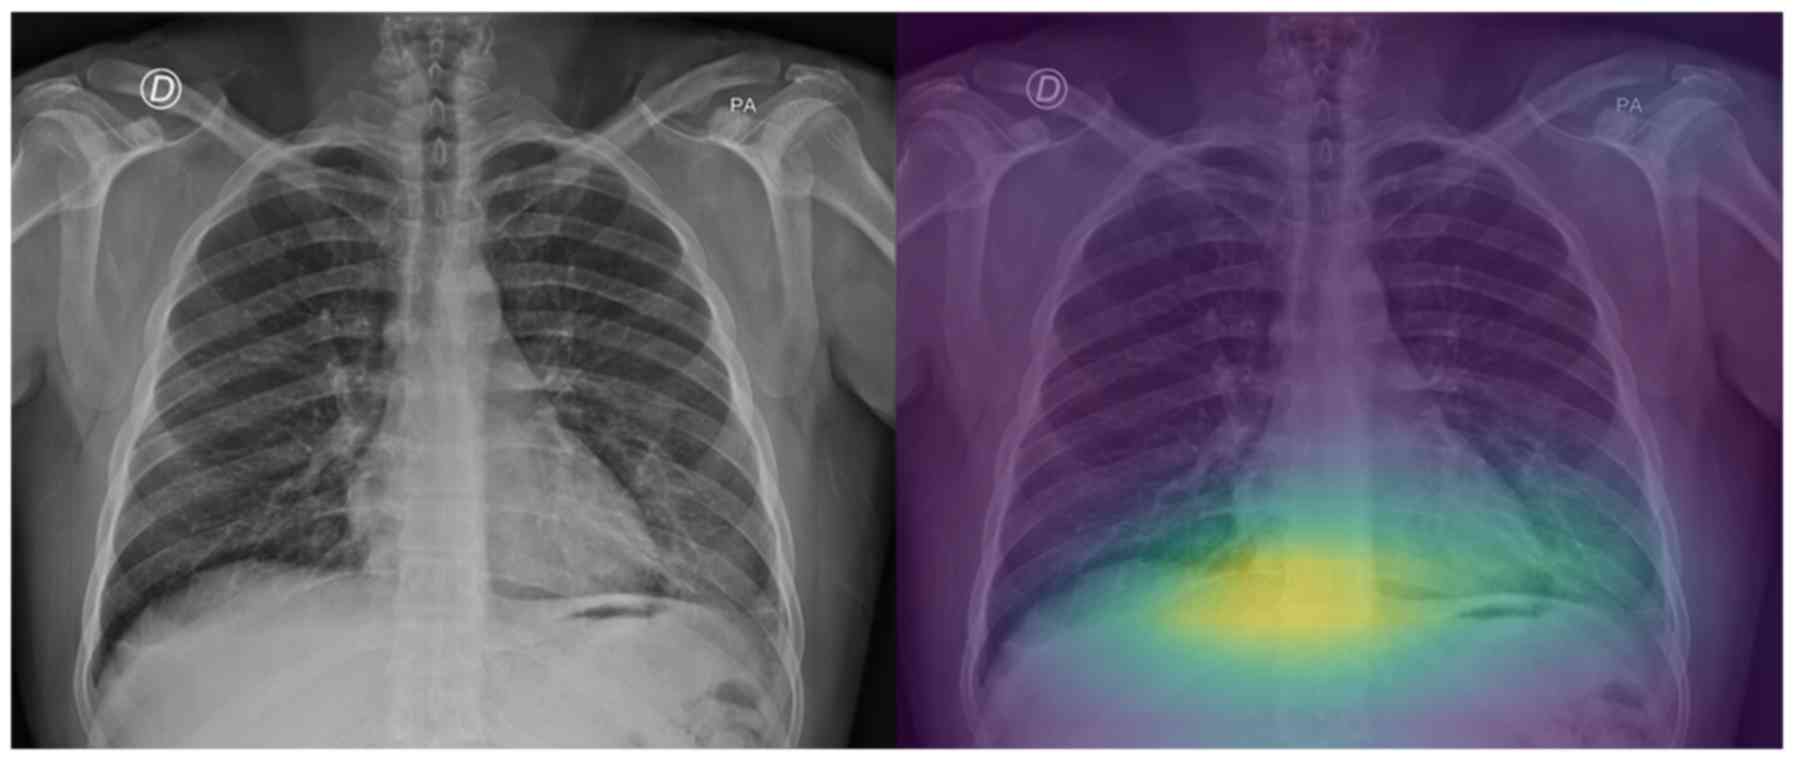

Interpretable artificial intelligence framework for COVID‑19 screening on chest X‑rays

COVID-19 has led to an unprecedented healthcare crisis with millions of infected people across the globe often pushing infrastructures, healthcare workers and entire economies beyond their limits. The scarcity of testing kits, even in developed countries, has led to extensive research efforts towards alternative solutions with high sensitivity. Chest radiological imaging paired with artificial intelligence (AI) can offer significant advantages in diagnosis of novel coronavirus infected patients. To this end, transfer learning techniques are used for overcoming the limitations emanating from the lack of relevant big datasets, enabling specialized models to converge on limited data, as in the case of X‑rays of COVID‑19 patients. In this study, we present an interpretable AI framework assessed by expert radiologists on the basis on how well the attention maps focus on the diagnostically‑relevant image regions. The proposed transfer learning methodology achieves an overall area under the curve of 1 for a binary classification problem across a 5‑fold training/testing dataset.